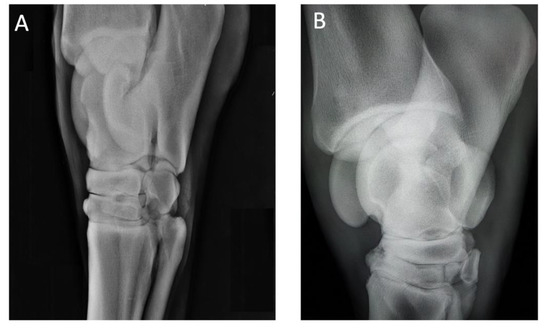

2.1. History and Case Presentation

| (1) 7-year-old S.I. gelding jumping horse | Navicular sindrome | Lameness Flexion test | 1 3 | 1 2 | 0 1 | 0 0 | 0 0 |

| (2) 16-year-old NRPS gelding jumping horse | Navicular syndrome and distal interphalangeal joint arthrosis of the right anterior limb | Lameness Flexion test | 3 3 | 2 3 | 2 2 | 1 1 | 0 0 |